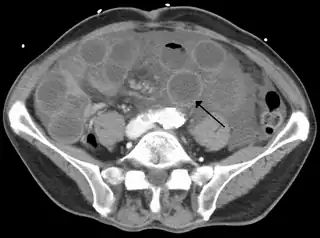

TC de una isquemia de intestino delgado debida a trombosis de la vena mesentérica superior. Se muestra el intestino dilatado y la pared engrosada.